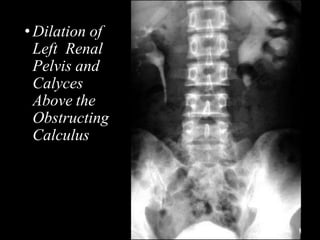

•Dilation of

Left Renal

Pelvis and

Calyces

Above the

Obstructing

Calculus